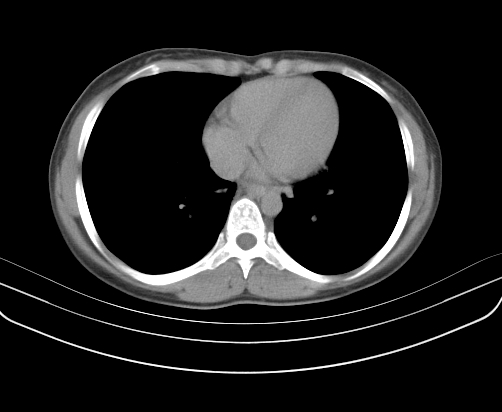

胸部